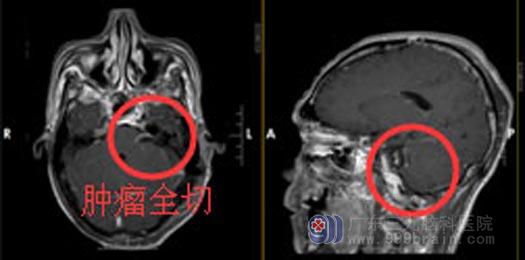

手术后

手术中,发现肿瘤位于左侧桥小脑角,黄白色,质中,显微镜下电凝分块切除,肿瘤卒中,听神经、面神经位于肿瘤前下方,经分离面神经保留完整,三叉神经、舌咽神经受肿瘤压迫明显,细心分离完整保留,脑干表面肿瘤粘连紧密,肿瘤基底部位于内听道,予反复电凝烧灼,术腔止血彻底,硬膜补片严密缝合硬膜,手术经过顺利.

术后,刘先生在家人和医护人员的悉心照料下,恢复迅速,没有留下后遗症。